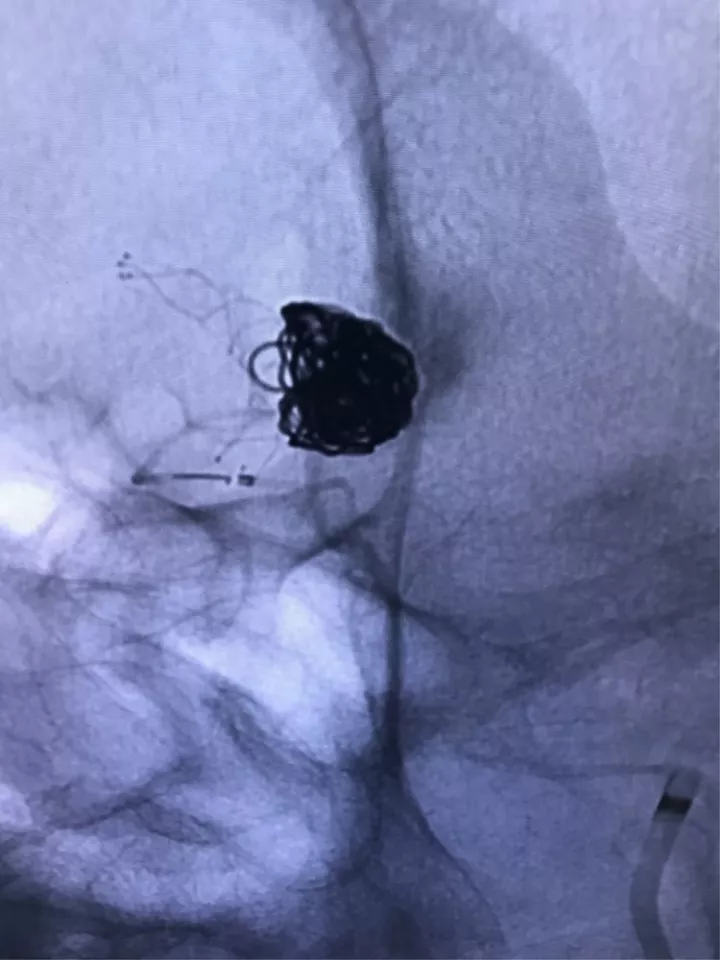

找到支架与弹簧圈之间的切线位,继续填塞。支架很好地保护住了颈内动脉和后交通动脉

最后的填塞结果

释放后的造影。突入颈内动脉和后交通动脉内的弹簧圈被压入瘤体内

继续填塞,后面就简单了。最后的结果,一共用了四枚弹簧圈,栓塞致密,瘤体及破口都不显影了

顺利完成手术。几点体会:1、支架要选用Enterprise或LVIS jr,好定位。2、支架末端够用就行,不能留得太长。3、弹簧圈不要先解脱,支架释放成功再解脱,一旦失败还有余地。4、推导管的时候要拽着支架推送杆,不要让支架提前意外解脱了。5、颈内动脉瘤颈以远太细或有狭窄的不建议。6、缺点是技术稍显复杂,优点是能很好的将瘤颈填致密,难度不大,适合的病例可以选择。在此感谢各位长期指导我的教授及专家。感谢冯雷教授的经验分享。